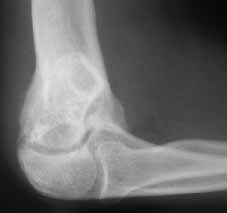

17 y/o female, had supracondylar elbow fracture in childhood which was treated by closed reduction and fixation with K-wires.

Now has elbow ROM 30-90 deg. Complaind moderate pain during activity.

I would not attempt to do anything arthroscopically here. There is much too much distortion of anatomy. I don't believe you will get her a greater arc of motion by any means. Her distal humerus is far too distorted and has developed that way. Her capitellum appears malaligned, pointing more distally than usual which is probably limiting her flexion, andthere is deformity to the ulnohumeral joint. The osteophytes are secondary, and removal may decrease some of her pain at the terminus of extension/flexion, but won't change her motion. Her arc of motion can be changed to allow her EITHER more flexionOR more extension, if an osteotomy is done, for instance- it might be moved to 60-120, or to 0-60 (not particularly functional). An osteotomy to correct the varus deformity will be cosmetic only, and one must be careful of injuring the median nerve.